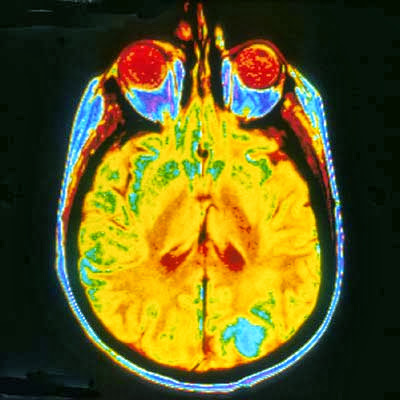

Die bildgebenden Verfahren der modernen Neurowissenschaften tragen dazu

bei, die vielfältigen Ursachen für menschliches Verhalten zu erforschen.

Mit ihrer Hilfe können Zusammenhänge zwischen Gehirnstruktur,

Gehirnfunktionen und unserem Handeln aufgezeigt werden.